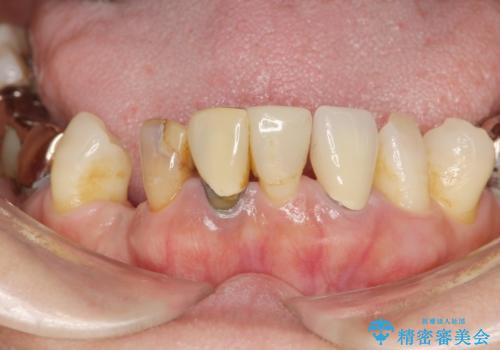

歯周病 全顎治療

- 前歯の見た目、入れ歯による噛めないことの改善を求めて来院されました。

検査により全顎的な歯周病治療、欠損のインプラント補綴、根管治療が必要な状態であることをお伝えし、治療を計画します。